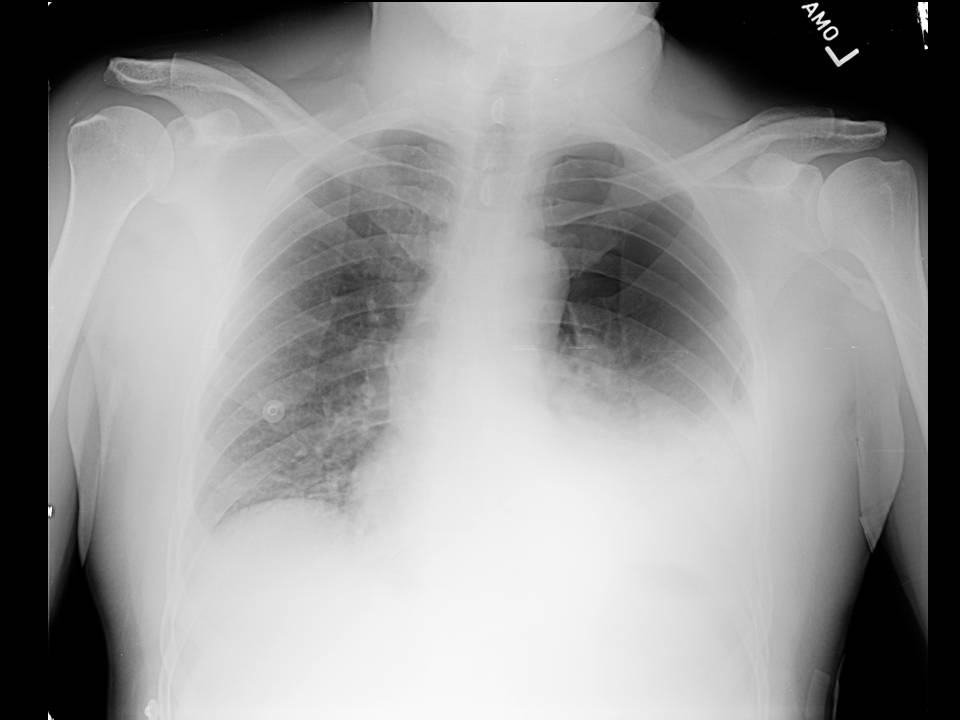

Ninety percent of spontaneous ruptures occur in the distal esophagus. Most occur on the left side just above the diaphragm, where the normal esophagus lacks serosal covering and there may be thinning of the muscularis mucosa. Seventy-five to 90% of spontaneous thoracic esophageal perforations are associated with left sided pleural effusions or hydropneumothorax, as seen in this patient (1).

Other radiographic findings seen in esophageal rupture include widening of the mediastinum, the presence of an air fluid level in the mediastinum, and in cases where the involved segment of esophagus is below the diaphragm, free air in the lesser sac or retroperitoneum may be seen (1).